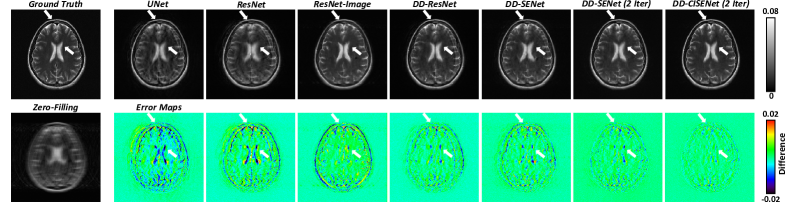

Figure 2: Visualizations of the reconstructed MRI images using predicted k-space. Difference maps are placed at the bottom side for comparison.

Fig.Β 2 shows the qualitative comparison of the reconstructed MRI images by multiple approaches. The proposed DD-CISENet outputs more accurate MRI images than existing image-domain prediction techniques (ResNet-Image), k-space synthesis methods (UNet, ResNet), and dual-domain feature fusion approaches (DD-ResNet, DD-SENet). TableΒ LABEL:tab:img lists the quantitative comparison of the generated k-space and reconstructed MRI images by multiple approaches using normalized mean square error (NMSE) and structural similarity (SSIM). It can be observed that DD-CISENet presents quantitatively more accurate k-space data and reconstructed MRI images than existing methods. Paired t-tests further validated the statistical significance of the quantification results (p<0.001𝑝0.001p<0.001). Thus, the proposed DD-CISENet demonstrated state-of-the-art performance in MRI sparse reconstruction, superior to existing image-domain, k-space, and dual-domain methods.